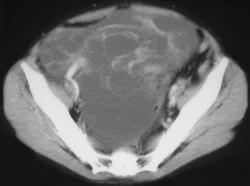

Gastric Lymphoma With Adrenal Involvement